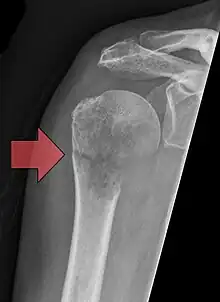

| Pathological fracture of the humerus in a patient with metastasis of renal cell carcinoma | |

A pathologic fracture is a bone fracture caused by weakness of the bone structure that leads to decrease mechanical resistance to normal mechanical loads.[1] This process is most commonly due to osteoporosis, but may also be due to other pathologies such as cancer, infection (such as osteomyelitis), inherited bone disorders, or a bone cyst. Only a small number of conditions are commonly responsible for pathological fractures, including osteoporosis, osteomalacia, Paget's disease, Osteitis, osteogenesis imperfecta, benign bone tumours and cysts, secondary malignant bone tumours and primary malignant bone tumours.

Pathological fractures present as a chalkstick fracture in long bones, and appear as a transverse fractures nearly 90 degrees to the long axis of the bone. In a pathological compression fracture of a spinal vertebra fractures will commonly appear to collapse the entire body of vertebra.